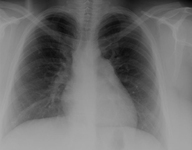

RT que demuestra una circulación pulmonar excesiva

Mayo Clinic Foundation